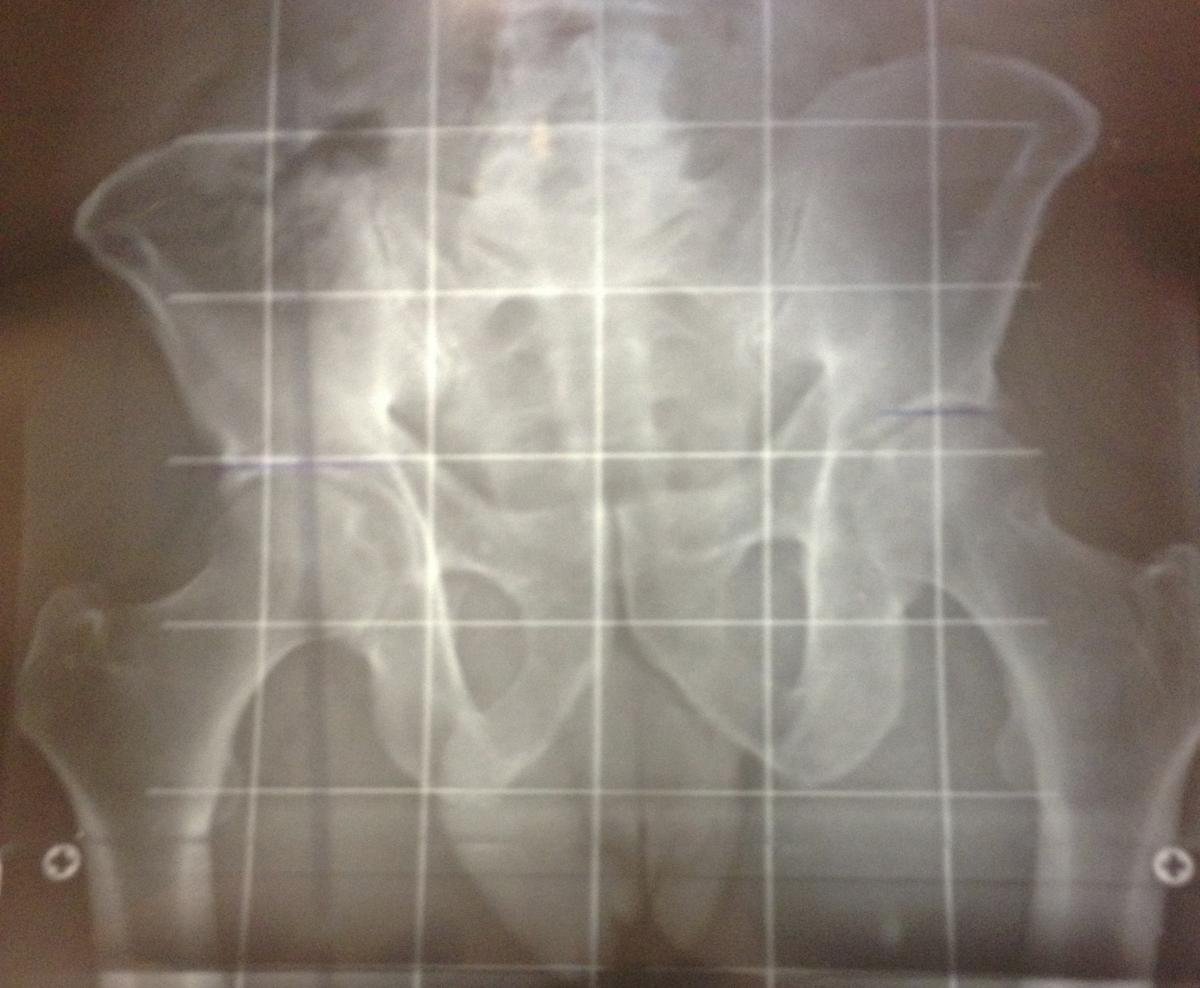

Telemetría, donde se puede apreciar la diferencia ósea de las extremidades inferiores del paciente

Ejemplo de caso clínico de dismetría de cadera

Esto es lo que le ocurrió a uno de nuestros pacientes que acudió a la consulta de Podoactiva aquejado por una fascitis plantar en un pie.

Desde Podoactiva, al realizar la exploración y revisión, se detectó una dismetría bastante acentuada que hasta entonces ningún especialista había percibido en el paciente. Las dismetrías son complejas de diagnosticar y existen diversas técnicas. Para ello, se utilizan procedimientos incluidos dentro del estudio biomecánico de la pisada, por ejemplo, el uso de plataforma de presiones tiene una gran precisión de diagnóstico y aportan un amplio abanico de parámetros.

El tratamiento prescrito para nuestro paciente, una vez obtenido el resultado de todas las pruebas, fue la prescripción de soportes plantares con alza en la pierna corta. Desde entonces, la evolución ha sido todo un éxito y el paciente ha podido volver a disputar carreras.